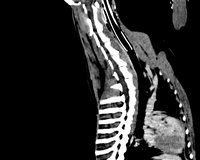

Axial Cuts - Lumbosacral Scanner of a dog - Sagital Reformatting. From the patient's native axial cuts, reconstruction software allows reformatting in all other planes (sagittal, coronal, or oblique). Finally, three-dimensional reconstructions can also be carried out with volume, surface, or endoscopic rendering.